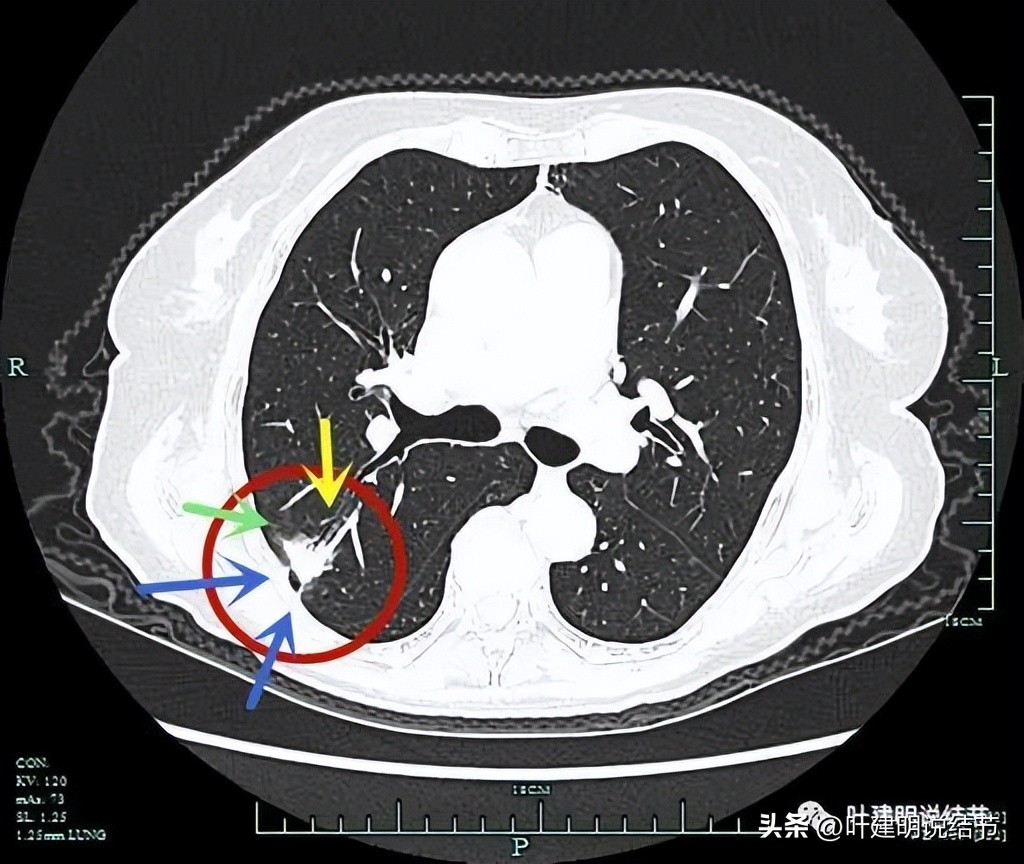

病灶有支气管截断(黄色箭头);边缘区域磨玻璃成分(绿色箭头);胸膜牵拉(蓝色箭头)。